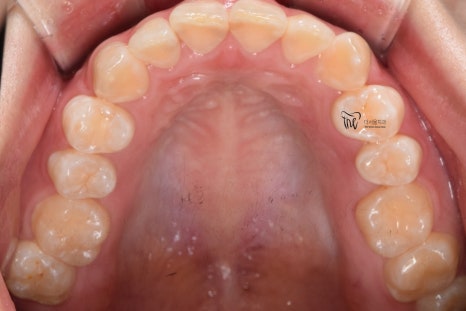

구강 내 사진을 보면, 전형적인 Open bite 의

형태를 띄고 있는 것을 보실 수 있습니다.

그 정도는, 그렇게 심하지는 않으나

치아교정 을 받지 않는다면 턱관절 에

더 큰 문제를 일으킨다는 것을 본인 스스로도

잘 알고 있었기 때문에 저에게 진료를

의뢰했었습니다.